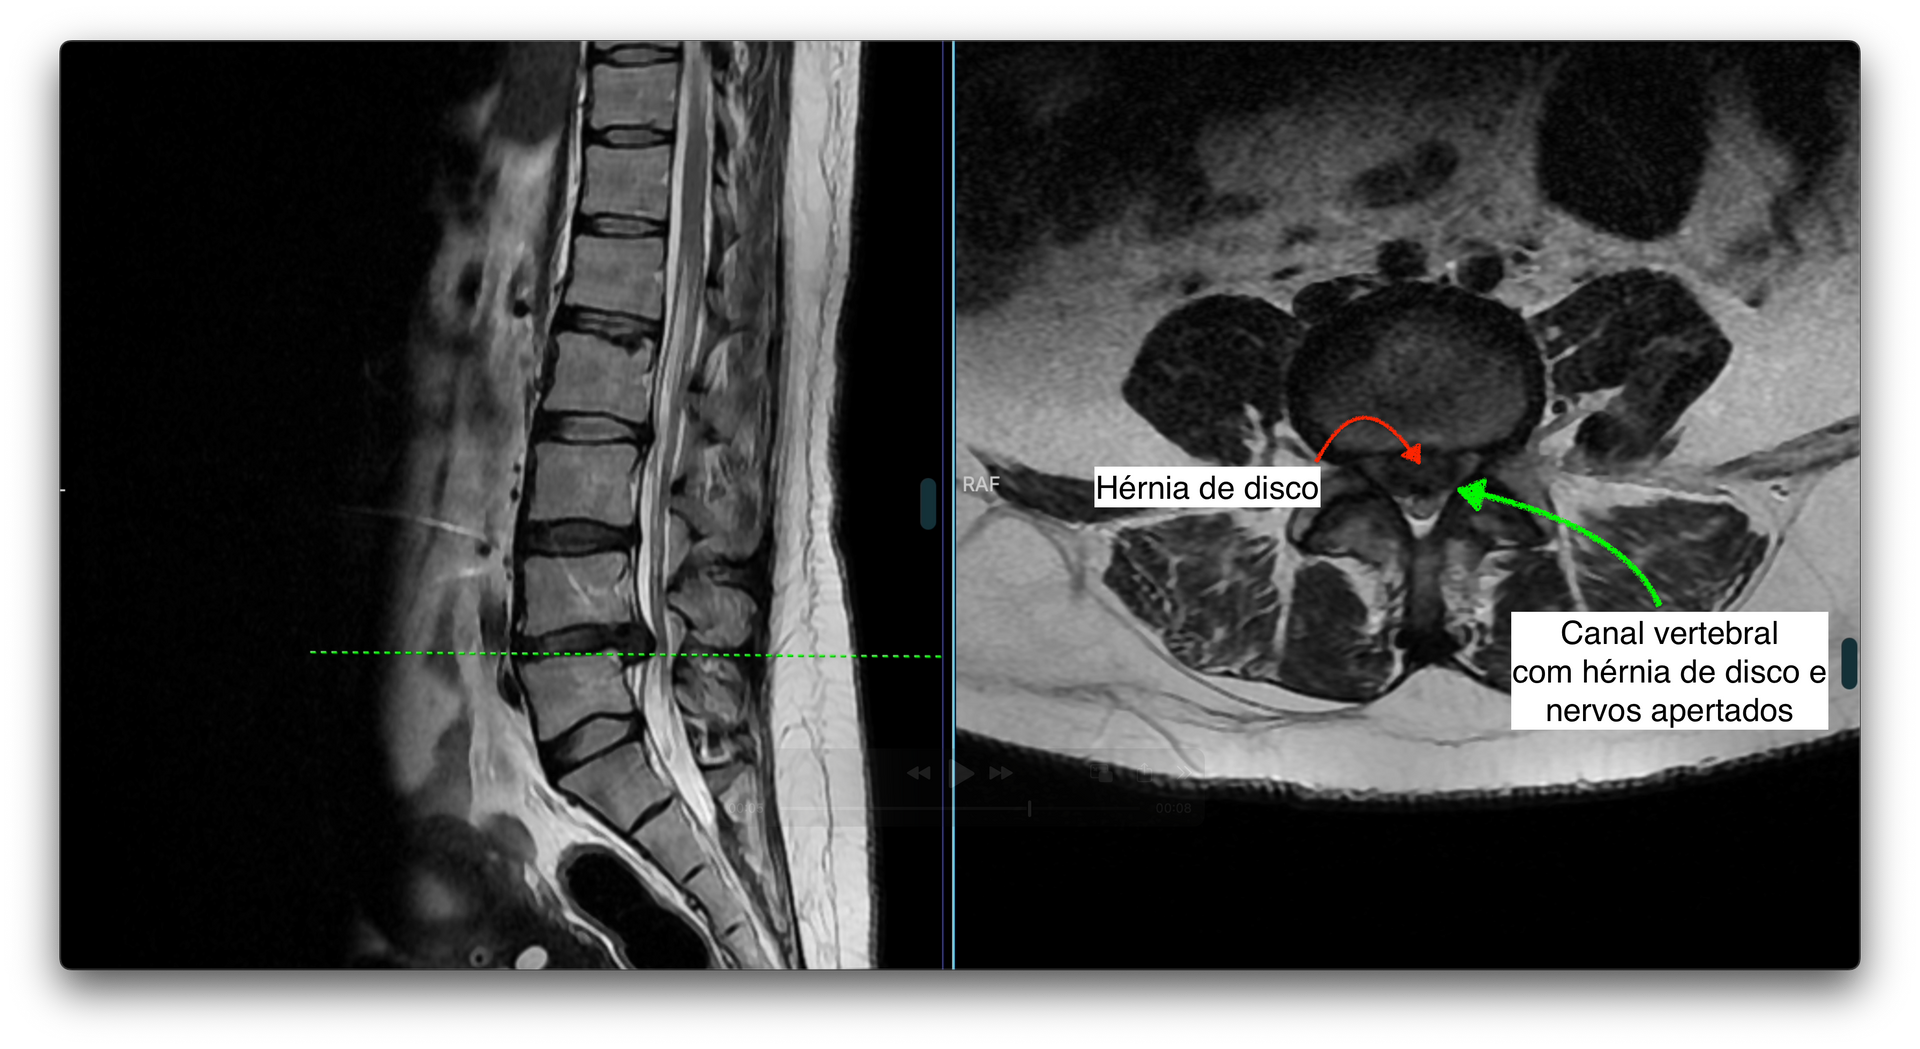

O principal exame de imagem é a ressonância magnética da coluna lombar, que mostra com detalhes a presença da hérnia, sua localização e se há compressão de raízes nervosas.

Entre as vértebras da coluna existe uma estrutura chamada disco intervertebral, que funciona como um amortecedor, permitindo mobilidade e absorvendo impactos. Esse disco é formado por um centro gelatinoso (núcleo pulposo) e uma parte mais resistente ao redor (ânulo fibroso).

Com o tempo, ou após sobrecargas repetitivas, o disco pode se desgastar e seu conteúdo interno pode se projetar para fora, formando o que chamamos de hérnia de disco. Quando isso acontece na região lombar (parte baixa das costas), chamamos de hérnia de disco lombar.

Essa hérnia pode comprimir estruturas nervosas próximas, como as raízes do nervo ciático, causando dor e outros sintomas.